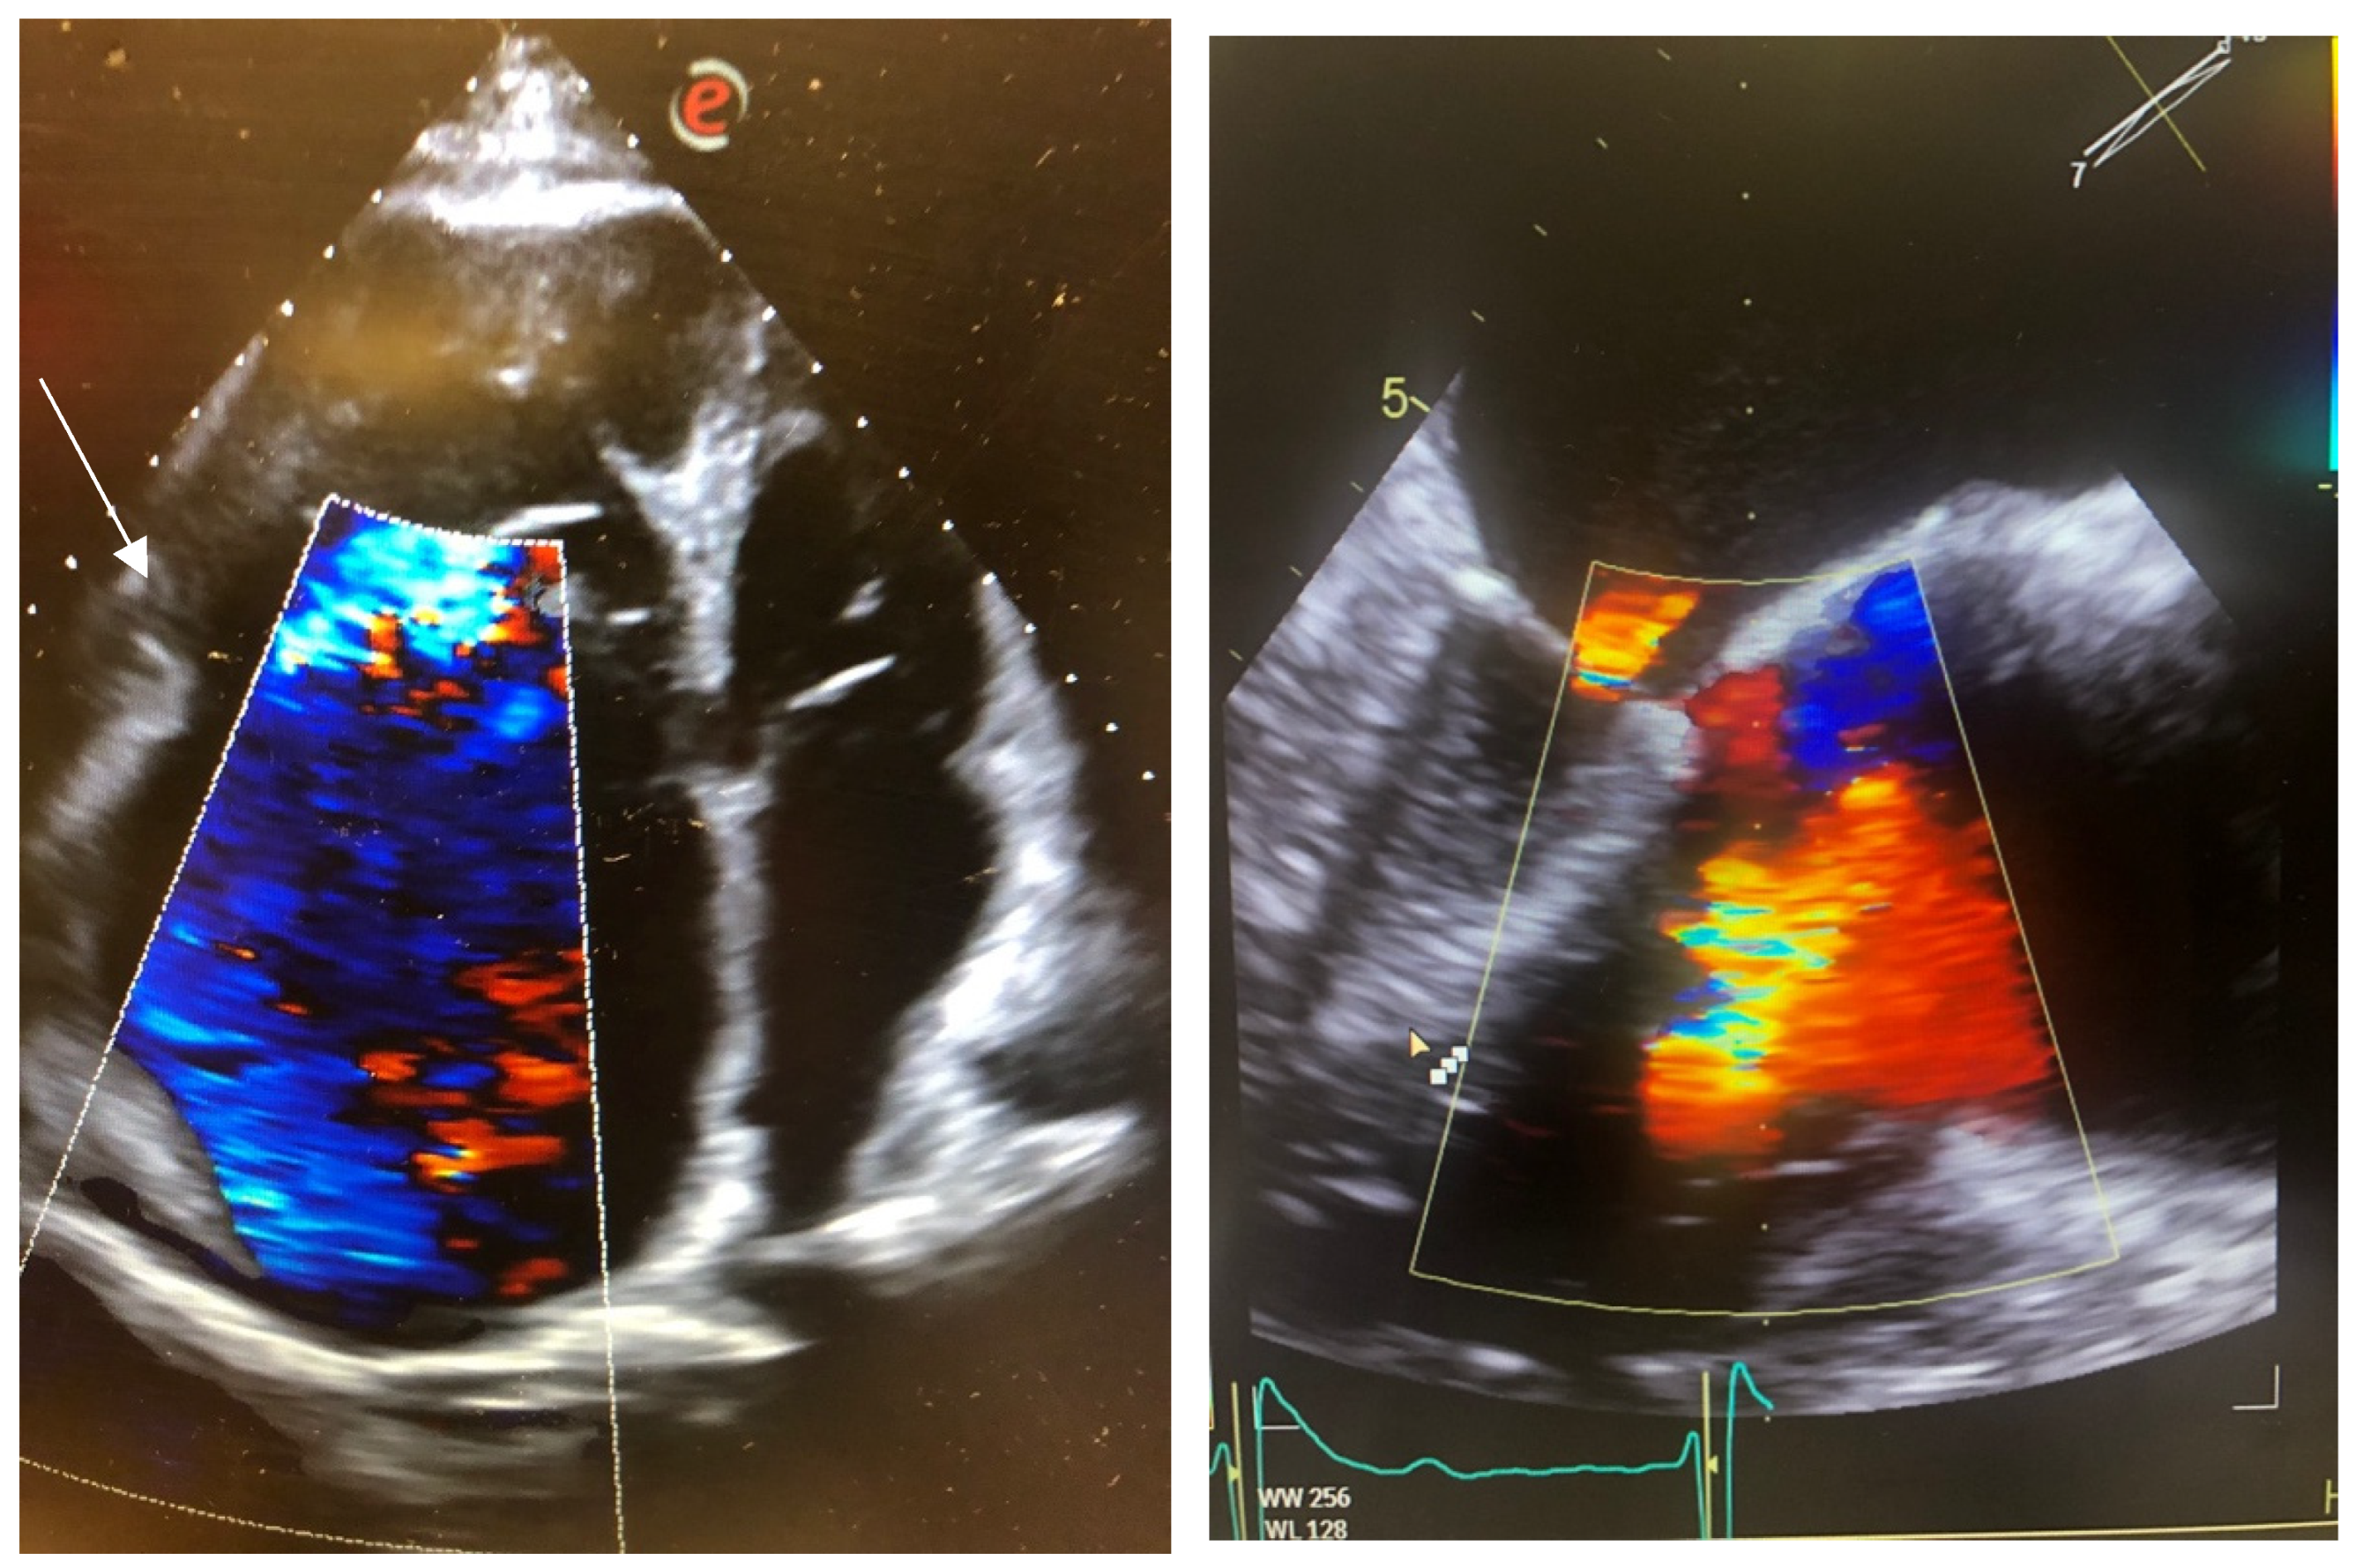

2.2. Case 2